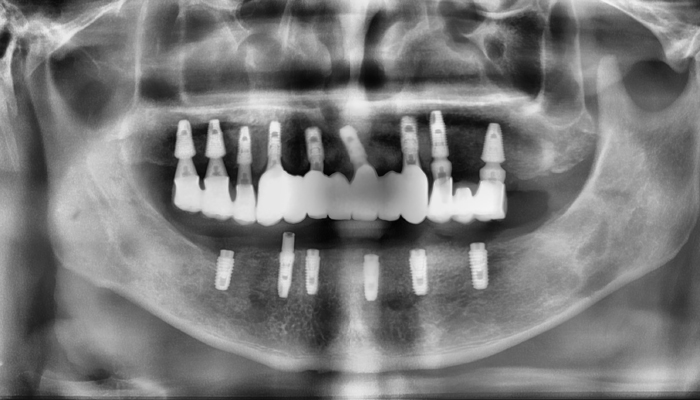

• 식립전

식립후